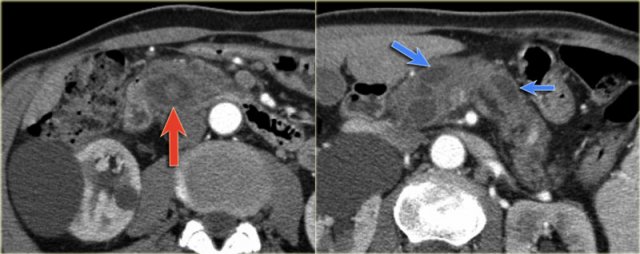

There is obstruction of the common bile duct with dilatation of the intrahepatic bile ducts (blue arrows).

Notice the extremely widened main pancreatic duct (red arrow).

CT-images of an IPMN with a dilated pancreatic duct (blue arrows).

Notice enhancing solid nodule in the pancreatic head (red arrow).

Continue with the ultrasound-image.

The US-image shows a large branch-duct component within the pancreatic head.